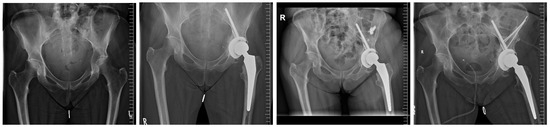

| Overall PRS implant size b (mm) | 56 ± 4 [52–68] |

| Tripolar acetabular systems; n (%) | 6 (50) |

| ->PRS® a implant size b (mm) | 60 ± 4 [56–68] |

| Cemented PE-Cup; n (%) | 6 (50) |

| ->PRS® a implant size b (mm) | 54 ± 2 [52–56] |

| Modular metal augments; n (%) | 2 (17) |

| Number of additional fixation screws b | 3 ± 1 [2–7] |

| Added screw lengths (mm) b | 161 ± 56 [100–290] |

| Lengths of 8 mm screw (mm) b | 90 ± 10 [70–100] |

| Added lengths of solely 6 mm screws (mm) b | 71 ± 56 [0–100] |